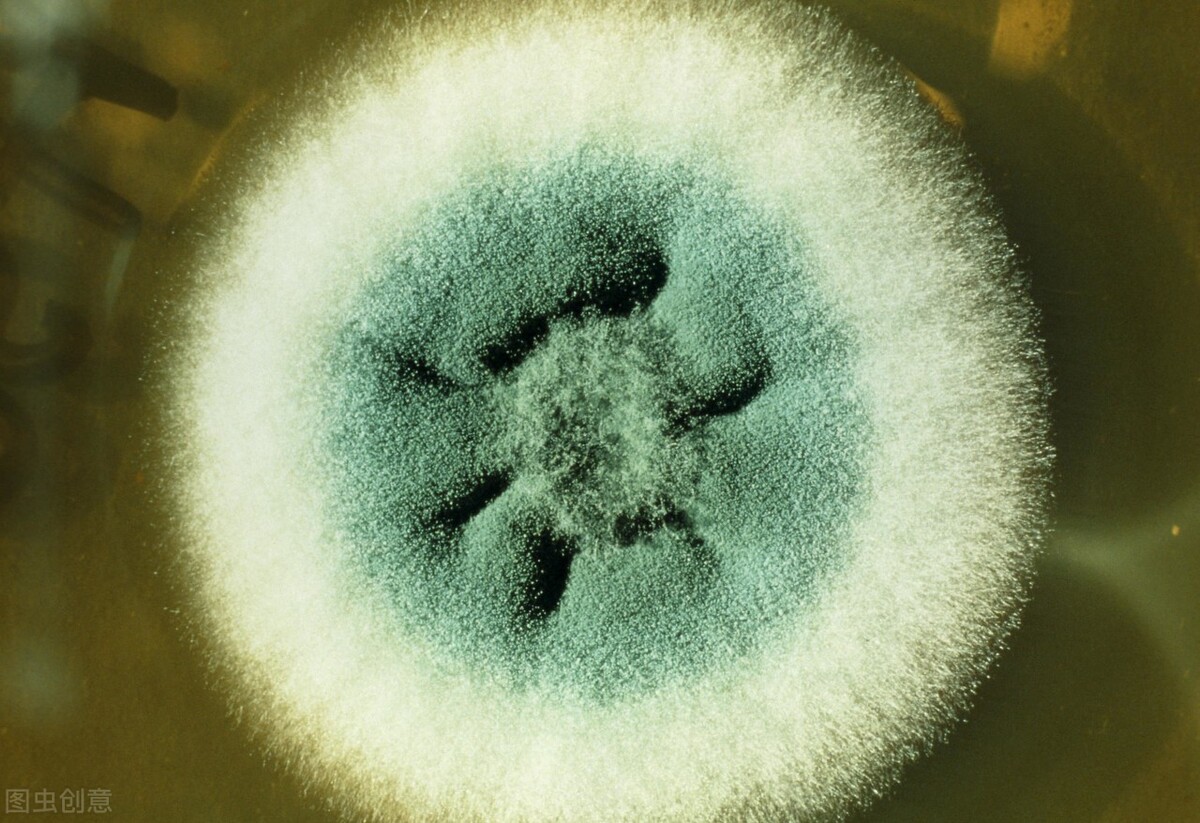

还别说,给这霉斑放大了,再加点美颜,还挺好看的,可惜长到气管里就让人开心不起来了。

上图这种烟曲霉分布广泛,几乎无处不在,因为它产孢能力强大(繁殖力强大),不论室内室外,每平方米空气孢子浓度可达1~100个,人类每天都能吸入100~1000个孢子(孢子类似于植物种子)。

而且烟曲霉胞壁富含疏水蛋白,易分散于空气中,且在一定湿度范围内变化不大,较其他同等大小的孢子更易被肺泡摄取。